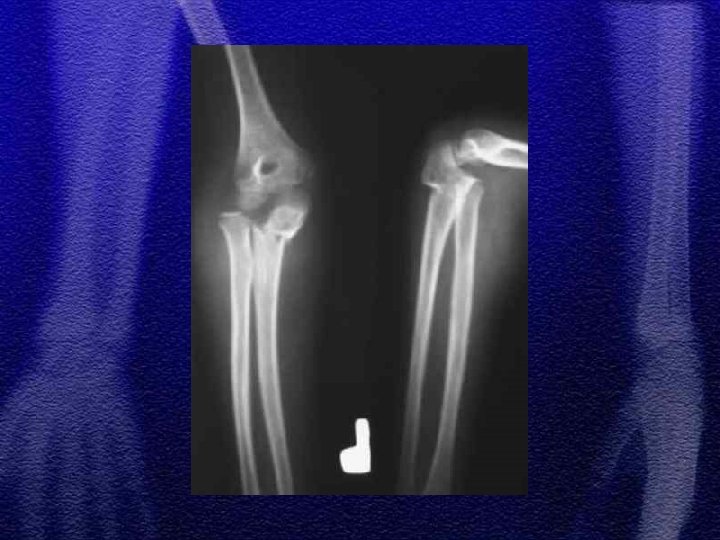

1. Jest to typ IV według Saltera-Harrisa 2. Mięśnie prostowniki, więzadło poboczne stawu łokciowego przemieszczają złamanie (złamanie awulsyjne) 3. Leczenie I° zachowawcze 4. II i III° operacyjne 5. Z uwagi na możliwość wtórnego przemieszczenia odłamów decydując się na leczenie zachowawcze należy pamiętać o kontrolach rtg. w 3, 7, 14 dobie od złamania

§ Występuje znacznie rzadziej aniżeli kłykcia bocznego § Jest to typ IV wg Saltera-Harrisa § Leczenie jak w złamaniach kłykcia bocznego

§ Ustawienie przedramienia w nadmiernej koślawości powoduje nadmierne pociąganie i oderwanie nadkłykcia przez mięśnie zginacze przedramienia § Jest uszkodzeniem awulsyjnym § Często towarzyszy zwichnięciu stawu łokciowego § Leczenie złamania z przemieszczeniem operacyjne

§ Izolowane występuje rzadko § Współistnieje ze złamaniem szyjki kości promieniowej lub złuszczeniem nasady bliższej kości promieniowej § Ze zwichnięciem głowy kości promieniowej (typ Monteggia) § Złamaniem kłykcia bocznego kości ramiennej § Leczenie - złamanie bez przemieszczenia zachowawcze, z przemieszczeniem operacyjne - grot Steinmanna, „popręg Webera”, śruba